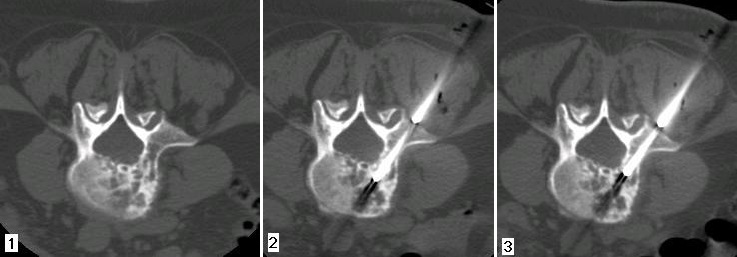

Figura 1 - La scansione TC dimostra un evidente rimaneggiamento osteostrutturale di tipo misto del corpo e del peduncolo di Ds di L4 in una paziente di 57 anni.

Figura 2 - I prelievo: la scansione TC dimostra l'esatto posizionamento della camicia introduttrice (8G) del set agobioptico e il corretto posizionamento dell'agobioptico (11 G) nel peduncolo.

Figura 3 - II prelievo: dopo aver estratto la prima 'carota' di tessuto si procede al II prelievo attraverso la camicia introduttrice che resta in situ ma che è stata inclinata in senso cranio-caudale per ottenere un'altra 'carota'; la scansione TC dimostra la posizione adeguata dell'agobioptico prima della sua estrazione. Diagnosi: metastasi da adenocarcinoma mammario di grado 3.